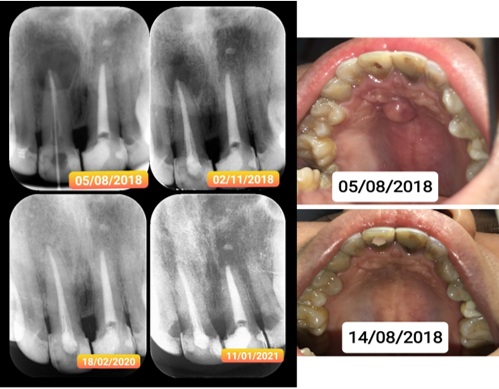

Kháng khuẩn mạnh mẽ: Đặc tính kiềm tính giúp tiêu diệt vi khuẩn hiệu quả, đặc biệt phù hợp cho các trường hợp nhiễm trùng quanh chóp nặng.

Tái tạo và phục hồi: Kích thích tạo ngà thứ phát, tái tạo xương và dây chằng nha chu, giúp bảo tồn răng thật tối đa.

• Trám bít ống tủy cho răng bị nhiễm trùng quanh chóp nặng.

• Điều trị các trường hợp răng bị ngoại tiêu nhờ khả năng phục hồi mô cứng vượt trội.